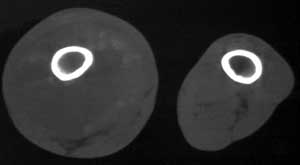

男56涨疼5-6月

右股骨下端包绕股骨见巨大软组织肿块,密度部俊,周围见瘤骨,下端骨皮质侵蚀变薄,骨质周围无骨膜反应, 考虑右股骨软骨肉瘤。

右股骨下段骨肉瘤,软组织内瘤骨,软组织肿块。